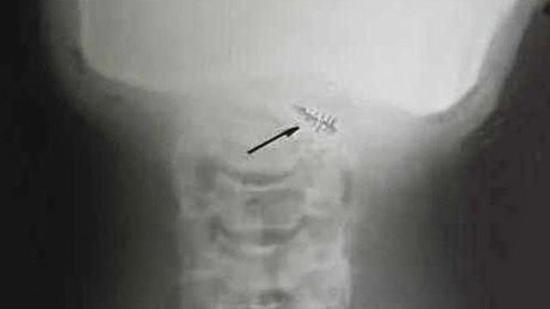

长久以来有许多人声称被外星人绑架,还有人他们被抓去做实验,并被植入不明物体。Roger Leir博士花上毕生时间研究取出这些物体,他说取出的不明物体都非常奇异,一般来说当有外物被植入人体时,人体会产生急性或慢性的肿胀现象,但这些人体却没有出现这些现象。这些金属物都被灰色类似肌肤的膜包覆著,有些甚至会在人体发出强烈的无线电,但一旦被取出就会消失。难道这些东西是有人为了吸引世人注意而做的吗?还是另有未知的物种在操控呢?